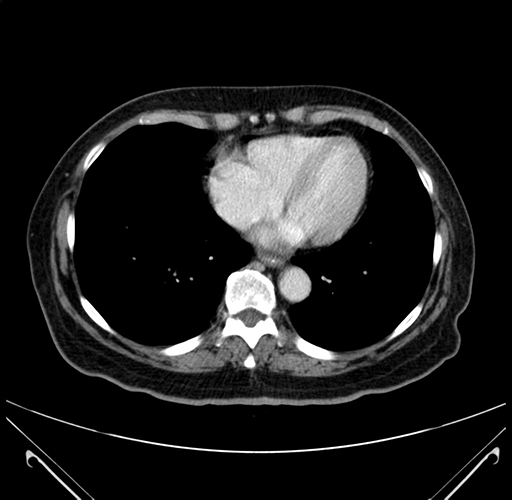

Pre-Chemo: Axial Venous

Axial Venous